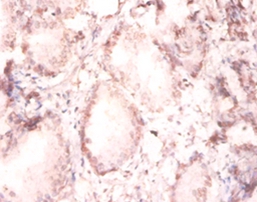

IHC (Immunohiostchemistry)

(Immunohistochemical analysis of paraffin-embedded human prostate using at dilution of 1:100.)